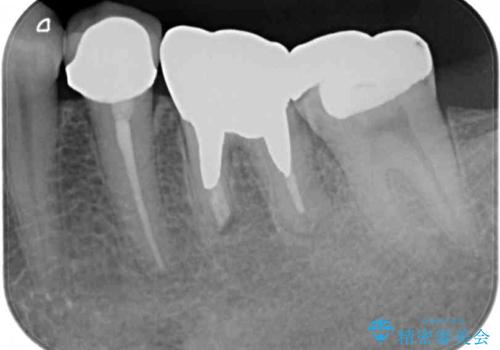

他にも、奥歯の銀歯の下にもむし歯が多くあり、痛みが生じていたため、根管治療などを行った上で、オールセラミッククラウンにて補綴治療することとしました。

前歯の裏側の接着面は、隙間ができていたことにより、汚れがたまるだけでなく、むし歯にもなっていました。

我々としては、治療により状態が悪化することだけは避けたいと考えているため、歯全体を覆うクラウンにすることで、より長持ちする治療を提供いたしました。

外観はもちろんのこと、隙間なく安心して咬むことのできる前歯となり、患者様には大変満足していただきました。